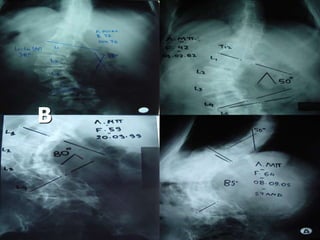

 Α. Παρ.

Θ – 15+3

Θ5 – Ο2 (Α) 40ο

King IV

 Θ. Κ.

Θ – 14

Θ5 – Θ12 (Δ) 55ο-

Ο1 - Ο4 (Α) 50ο

 Ε. Βαρ.

Θ – 13+0

Θ10 – Ο3 (Δ) 45ο

 King IV